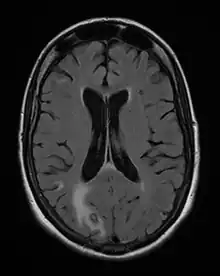

On décrit de rares cas où un sujet VIH+, sans immunité anti-toxoplasmique (pas de contact antérieur) contracte une toxoplasmose, mais le plus souvent il s'agit de patients immunisés contre la toxoplasmose, donc porteurs de kystes qui réactivent l'infection lors d'une baisse conséquente de leurs défenses immunitaires ; généralement, ils présentent une toxoplasmose cérébrale.

La toxoplasmose cérébrale est une maladie opportuniste dont la survenue chez les personnes séropositives marque l'évolution de l'infection par le VIH au stade de sida. Elle survient en règle générale chez des sujets séropositifs au VIH, ayant moins de 200 lymphocytes T CD4+, avec une sérologie toxoplasmique positive et ne recevant pas de prophylaxie spécifique. C'est alors que les bradyzoïtes libèrent les tachyzoïtes qui essaiment dans tout le corps via le système sanguin[37]. En 2008 en France, la toxoplasmose cérébrale représentait 12 % des personnes qui découvraient leur séropositivité au VIH après le déclenchement d'une affection opportuniste[38].